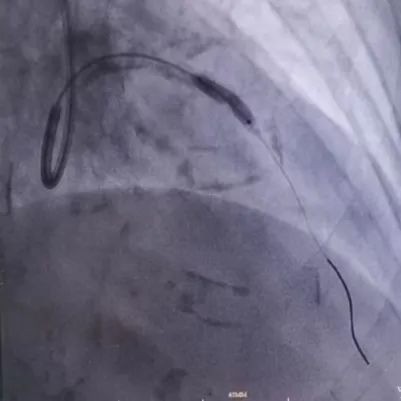

手术由黄进宇童国新两位教授联合实施。首先在前降支病变处置入3.5×12mm冲击波球囊,以4atm压力膨胀紧贴血管壁,然后启动脉冲发生器,持续激发10个脉冲完成第1周期,可见球囊逐渐膨胀充分,随后以6atm扩张冲击波球囊,可见球囊扩张满意。重新定位冲击波球囊,重复启动脉冲,总共7个周期脉冲优化冲击波碎石效果。

复查IVUS清晰可见病变处环形钙化多处断裂,局部未见明显夹层,获得较大管腔,已满足支架植入条件。遂于左前降支近段成功植入3.0×18mm、3.5×15mm药物洗脱支架2枚。复查造影及IVUS提示支架膨胀良好,未见夹层及边支丢失,手术取得圆满成功。

图4.支架植入后冠脉造影及IVUS图像